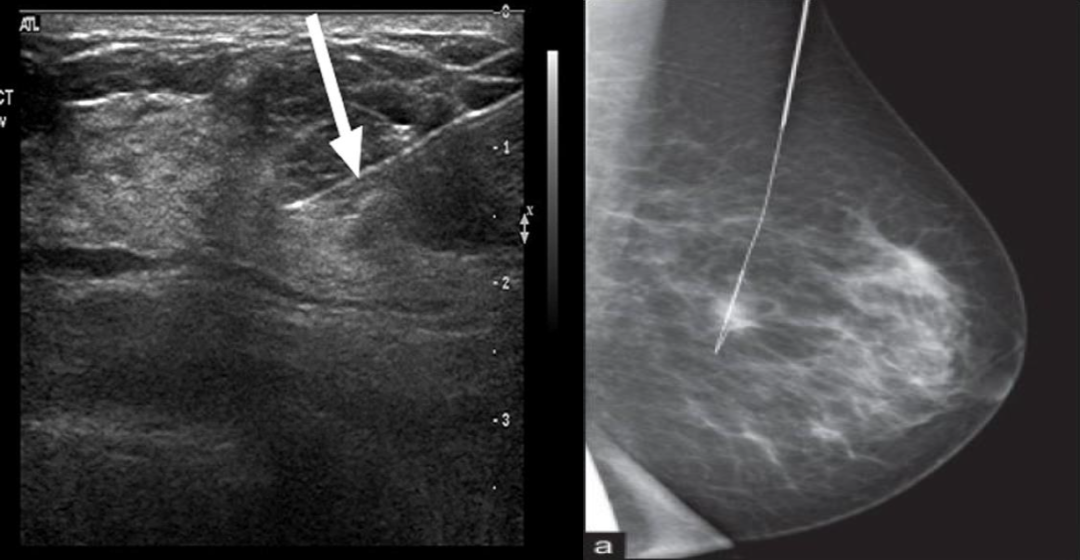

左右图分别为乳腺肿物超声图和 X 线图,内均可见金属定位导丝影

图片来源:www.thebreastonline.com,www.cancerjournal.net